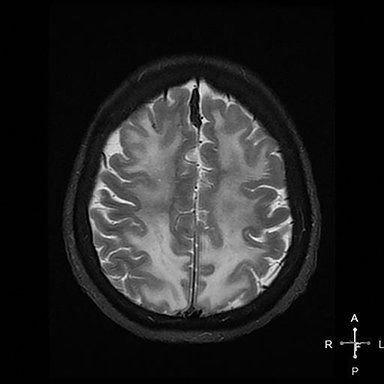

What's your diagnosis for this 64-year-old woman with history of inhaled heroin? See full case details here: http://ow.ly/OxSc30duhuF pic.twitter.com/NHRR3qQCW1